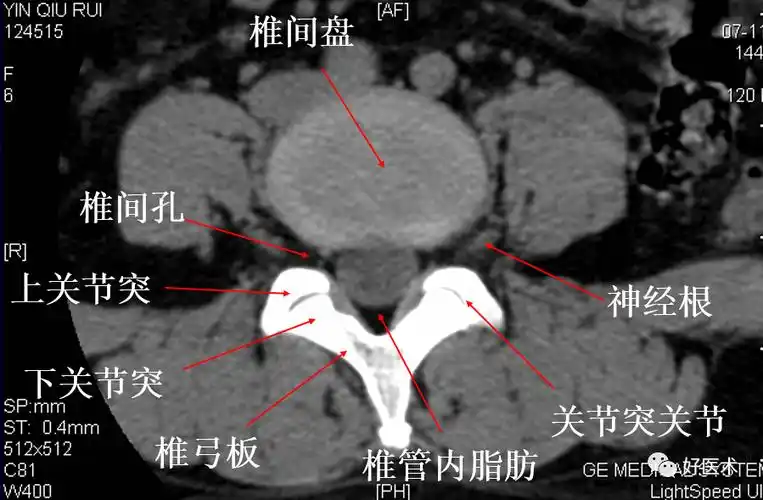

腰椎ct诊断